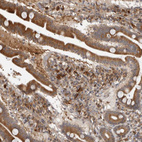

Immunohistochemical staining of human lymph node shows strong cytoplasmic positivity in lymphoid cells.